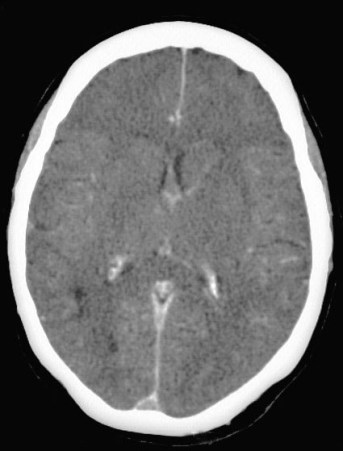

SIGNO DEL TRIÁNGULO DENSO

Este es un signo visible en la TC craneal sin contraste intravenoso, que consiste en un área triangular de alta densidad localizada en la zona del seno sagital superior, es decir en la línea media posterior de la caja craneal. Representa el trombo ocupando el seno venoso.

La hiperdensidad, como en el signo de la arteria cerebral media hiperdensa y otros signos afines, se debe a que el trombo presenta una mayor densidad que la sangre circulante debido a una mayor cantidad de fibrinógeno y proteínas y a una menor cantidad de suero.